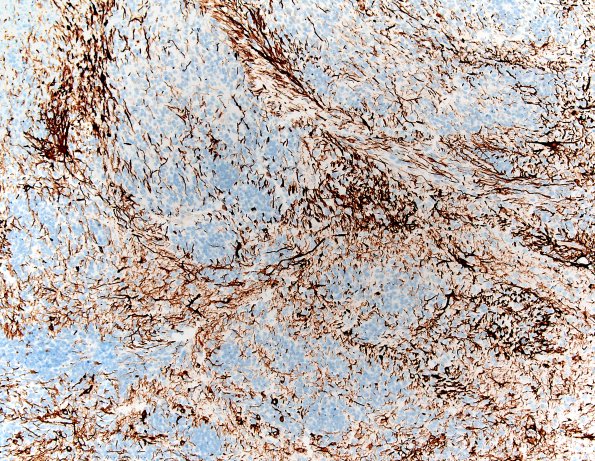

8E2-4 There are numerous GFAP-positive processes interspersed throughout the neuropil-like areas and scattered individual tumor cells are strongly positive. (GFAP IHC)